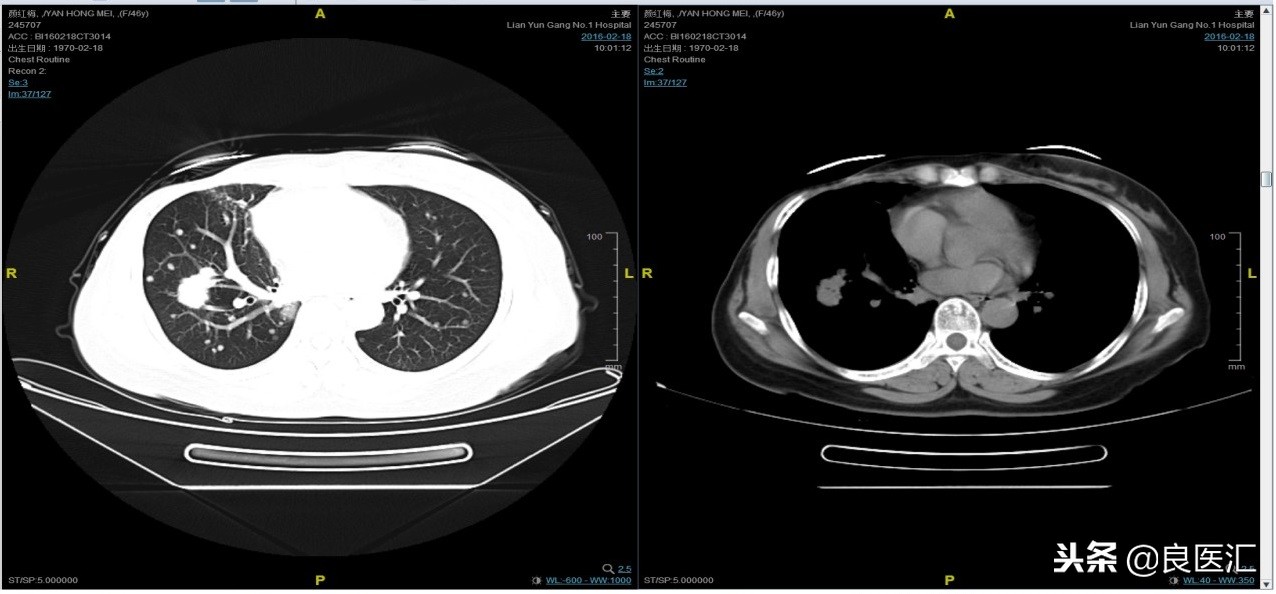

随访至2016-2-18,肺部病灶进展,肺内转移病灶增多。PFS2=10个月。

三线解救治疗及评价

从2016-2-19开始给予紫杉醇+曲妥珠单抗治疗,紫杉醇240mg,3周重复,曲妥珠单抗330mg三周重复。患者末次应用曲妥珠单抗和紫杉醇时间为2016-6-24,紫杉醇共应用4周期。